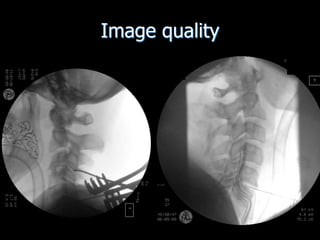

Image quality

• Is this image

diagnostic?

• Is this an

optimum

image?